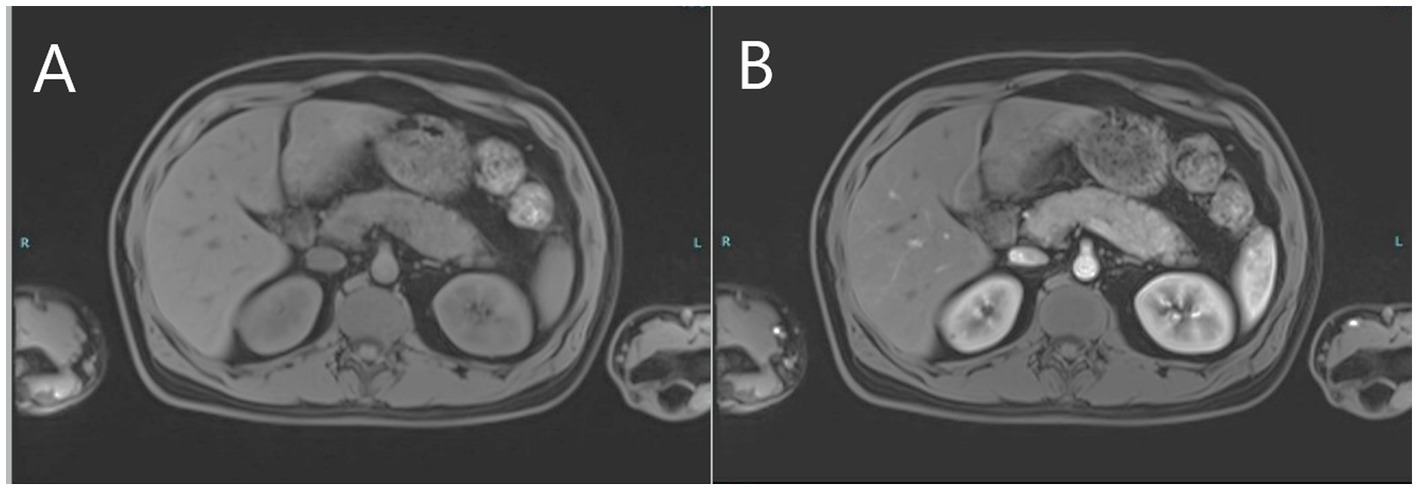

Figure 3

MRI images of the upper abdomen depicting pre-contrast bulky pancreas (A) and post-contrast delayed diffuse homogenous enhancement of the pancreas (B) consistent with autoimmune pancreatitis.

The patient continued to complain of recurring severe upper abdominal pain consistent with an unresolved clinical picture of pancreatitis as amylase and lipase levels remained high. Magnetic resonance cholangiopancreatography (MRCP) and contrast-enhanced MRI of the abdomen performed 10 days after initial presentation revealed a diffusely-enlarged, bulky pancreas showing delayed diffuse homogenous enhancement with no clear evidence of foci of necrosis or abscess formation (Figures 3A,B). There were no abnormalities suggestive of primary sclerosing cholangitis or pancreas divisum. Findings were deemed consistent with AIP. Serum IgG4 level was normal. In the presence of concomitant inflammatory bowel disease, the patient was diagnosed as “probable” type 2 AIP according to the International Consensus Diagnostic Criteria (ICDC) for AIP due to the absence of pancreatic biopsy (4).

The patient has UC-like colitis as confirmed by endoscopy and histopathology with typical features of mucosal neutrophilic infiltration, cryptitis, crypt abscesses, and basal plasmacytosis (5). A rapid response to steroid treatment also supports a diagnosis of immune-mediated (autoimmune) colitis. He also presented with a clinical picture of acute pancreatitis. He did not give a history of alcohol consumption or any medication that could potentially trigger acute pancreatitis, and there was no hypertriglyceridemia or hypercalcemia. Furthermore, MRCP and MRI confirmed the presence of a bulky pancreas showing delayed contrast enhancement, with no abnormalities such as pancreas divisum. Serum IgG4 was negative. In the presence of underlying UC-like colitis, it is reasonable to consider AIP as the most likely diagnosis.